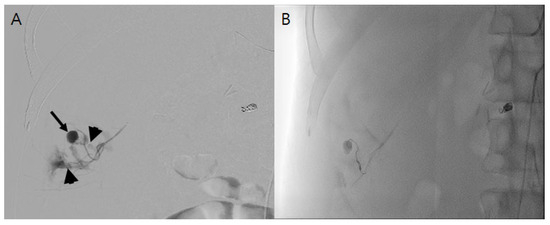

A normal saline infusion of 100 cc/h was started, and 400 mL of packed red blood cells (RBCs) was transfused for the control of his hypovolemic shock. An aortography and arteriography performed 2 h after the CT scan detected a pseudoaneurysm and the diffuse leakage of contrast media from the right 12th ICA (Figure 2A), while no aneurysmal change in the ICA was observed. After the super-selection of the bleeding artery by a microcatheter, embolization was performed using a detachable coil and gelfoam. In a subsequent arteriogram, additional contrast leakage was no longer detected (Figure 2B).

Figure 2. (A). Angiogram of subcostal artery shows pseudoaneurysm (black arrow) and diffuse contrast extravasation from it indicating active bleeding (arrowhead). (B). After embolization using gelfoam by super-selection of the bleeding artery, there was no additional contrast extravasation.